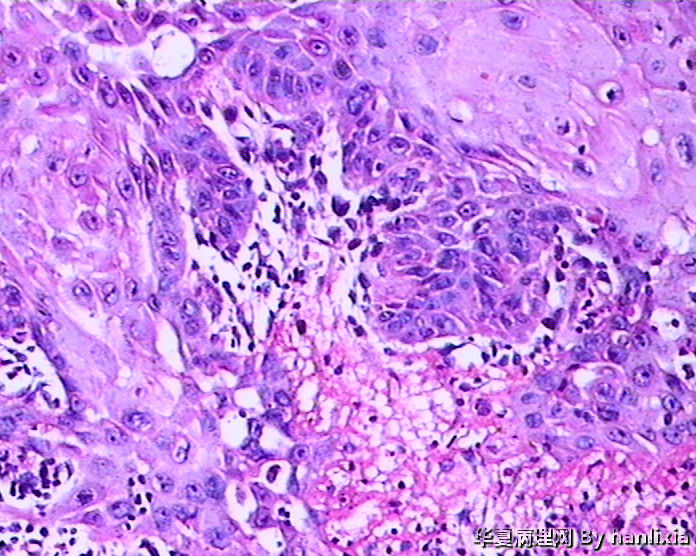

男性患者,50岁,发现面部皮肤(耳旁)肿物一年余,色黑。

高分化鳞状细胞癌

高分化鳞癌可能,也可能AK基础上发展而来的浅表型鳞癌?

部分区域突破基底膜,应该诊断鳞癌,由日光性角化发展过来的!